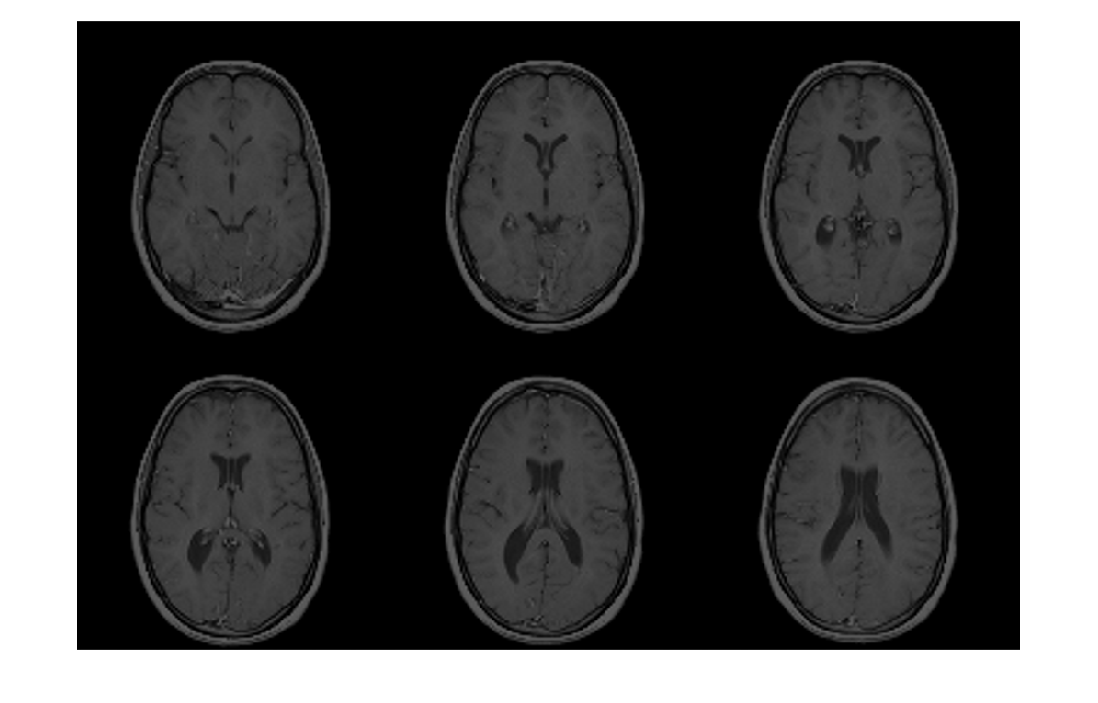

Analyze 7.5 のデータセットのイメージ ファイルからイメージ データを読み取る

は、文字ベクトル X = analyze75read(filename)filename により指定された Analyze 7.5 の形式のデータセットのイメージ ファイルからイメージ データを読み取ります。関数は、X のイメージ データを返します。

Analyze 7.5 は、メイヨー クリニックの医用画像リソース (Biomedical Imaging Resource) によって開発された、3 次元医用画像の可視化と解析を行うための製品です。Analyze 7.5 のデータセットは、ヘッダー ファイルとイメージ ファイルの 2 つのファイルで構成されています。ファイルは同じ名前ですが、拡張子が異なります。ヘッダー ファイルの拡張子は .hdr で、イメージ ファイルの拡張子は .img です。